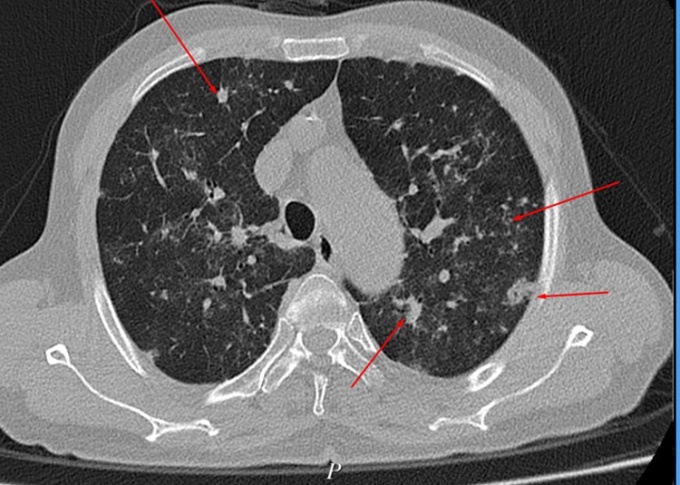

Các bác sĩ Bệnh viện Đa khoa Hùng Vương ngày 9/4 cho biết kết quả chụp CT lồng ngực bệnh nhân cho hình ảnh phổi đông đặc, tổn thương lan tỏa hai phổi do di chứng Covid. Bệnh nhân đang được điều trị tích cực và theo dõi sát tình trạng tổn thương phổi.

Hình ảnh phổi bệnh nhân đông đặc, tổn thương lan tỏa. Ảnh: Bệnh viện cung cấp